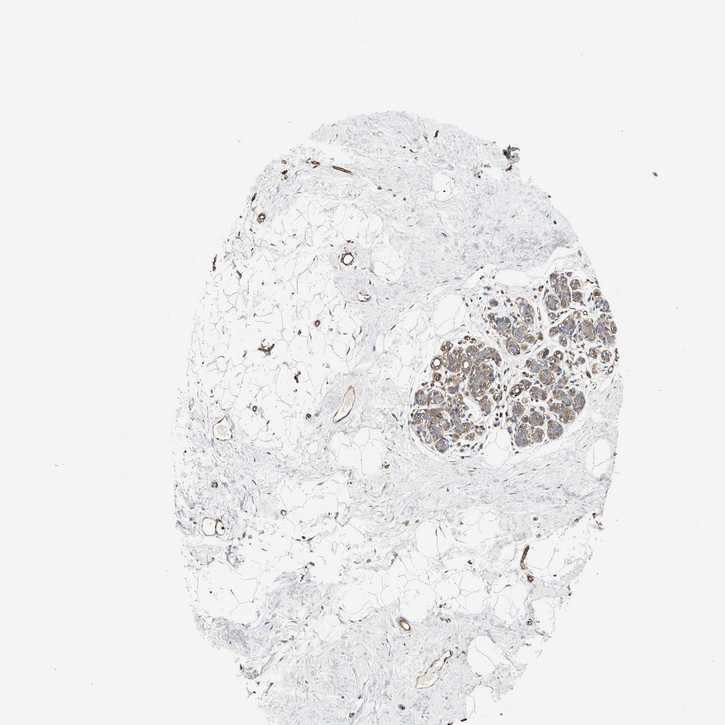

BREAST - Antibody stainingi

Antibody staining in the annotated cell types in the current human tissue is reported as not detected, low, medium, or high, based on conventional immunohistochemistry profiling in selected tissues. This score is based on the combination of the staining intensity and fraction of stained cells.

Each image is clickable and will lead to virtual microscopy that enables deeper exploration of all samples and also displays staining intensity scores, fraction scores and subcellular localization as well as patient and tissue information for each sample.

Antibody HPA013606Antibody HPA017964Antibody CAB015334Antibody CAB016402

Adipocytes LowMediumMediumMedium

Glandular cells MediumMediumMediumHigh

Myoepithelial cells MediumMediumMediumHigh